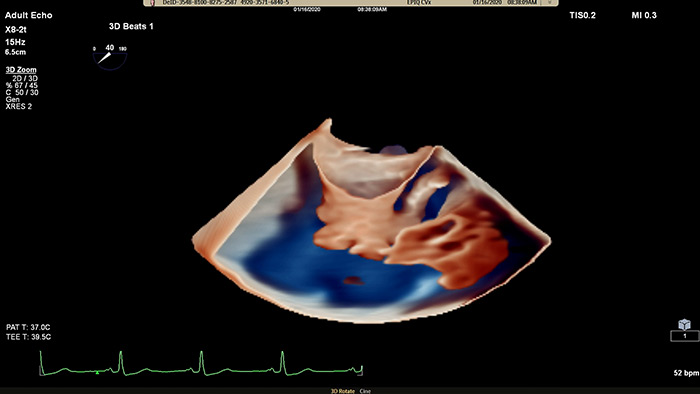

EPIQ CVx - TrueVue Color

View enhanced visualizations of structures and flow with TrueVue Color

EPIQ CVx - TrueVue Glass

Visualize cardiac morphology using ultrasound with TrueVue Glass